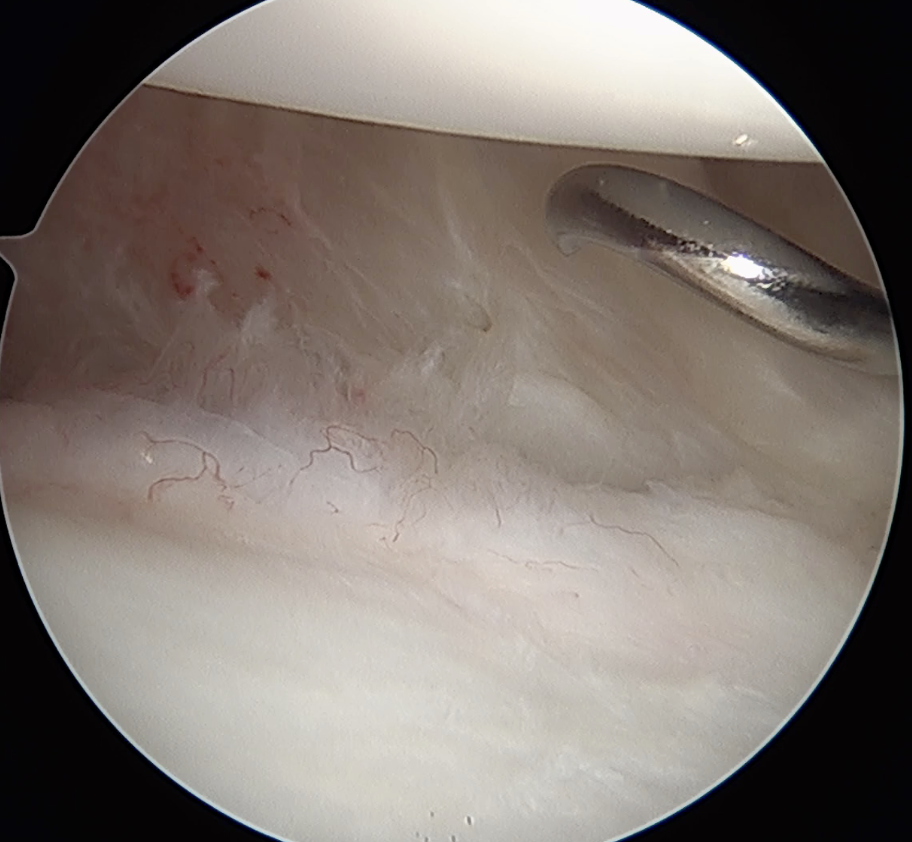

Technique

Vumedi shoulder plication for anterior instability video

Shoulder arthroscopy

- reduce capsule volume with sutures

- capsulorraphy

- can tie sutures to labrum

- can insert glenoid anchors to advance capsule